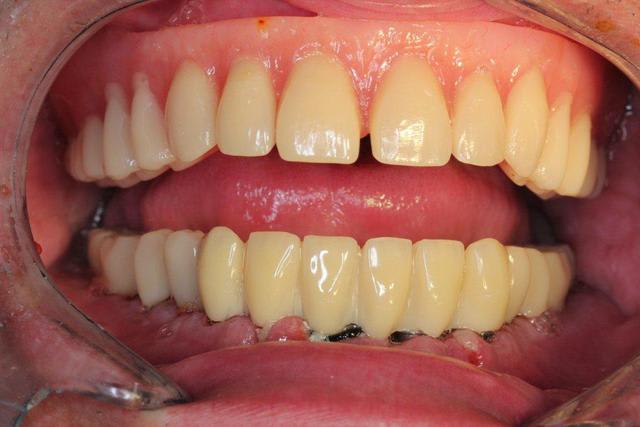

Juste pour vous dire à tous que je vis toujours

Un gros rail d os et tout posé à main levée

Ds 6 mois on fait le maxillaire

Ton patient va mourir d'une overdose de titane ;-)

Sérieusement, je m’interroge sur la validité bio-mécanique de placer 13 implants à la mandibule, et de tout relier cela d'un bloc.

Je crois que 8 implants soient amplement suffisants : meilleur espacement entre les implants pour l'entretient et la maintenance paro